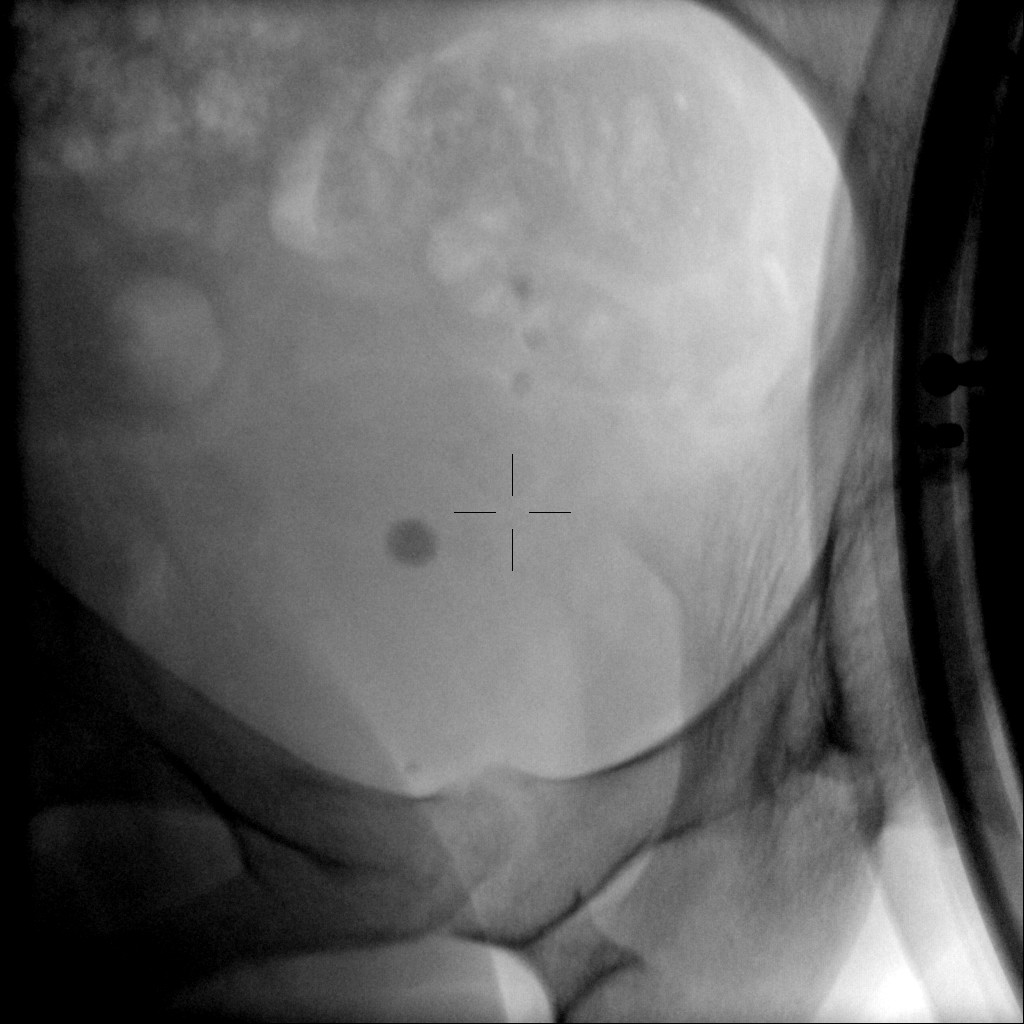

Complete fragmentation of a distal ureteral stone by #ESWL. Radiological and Ultrasound verification. Small stones are also fun!! @FPuigvert @oangerri @koey_kana @paoloverri05 @a_bravo_balado @joanfundi